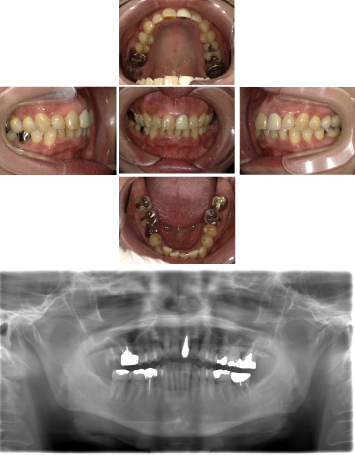

50代 女性 インプラント治療(GBR・ソケットリフト)

| 年代・性別 | 50代・女性 |

|---|---|

| 主訴 | Brの歯が取れそうなため、インプラントに変えたい。 |

| 部位 | 左下567 左上④5⑥ 右上67 |

| 治療期間 | 約3年9ヶ月 |

| 費用 | ¥3,224,500(税込) |

| 副作用・リスク |

|